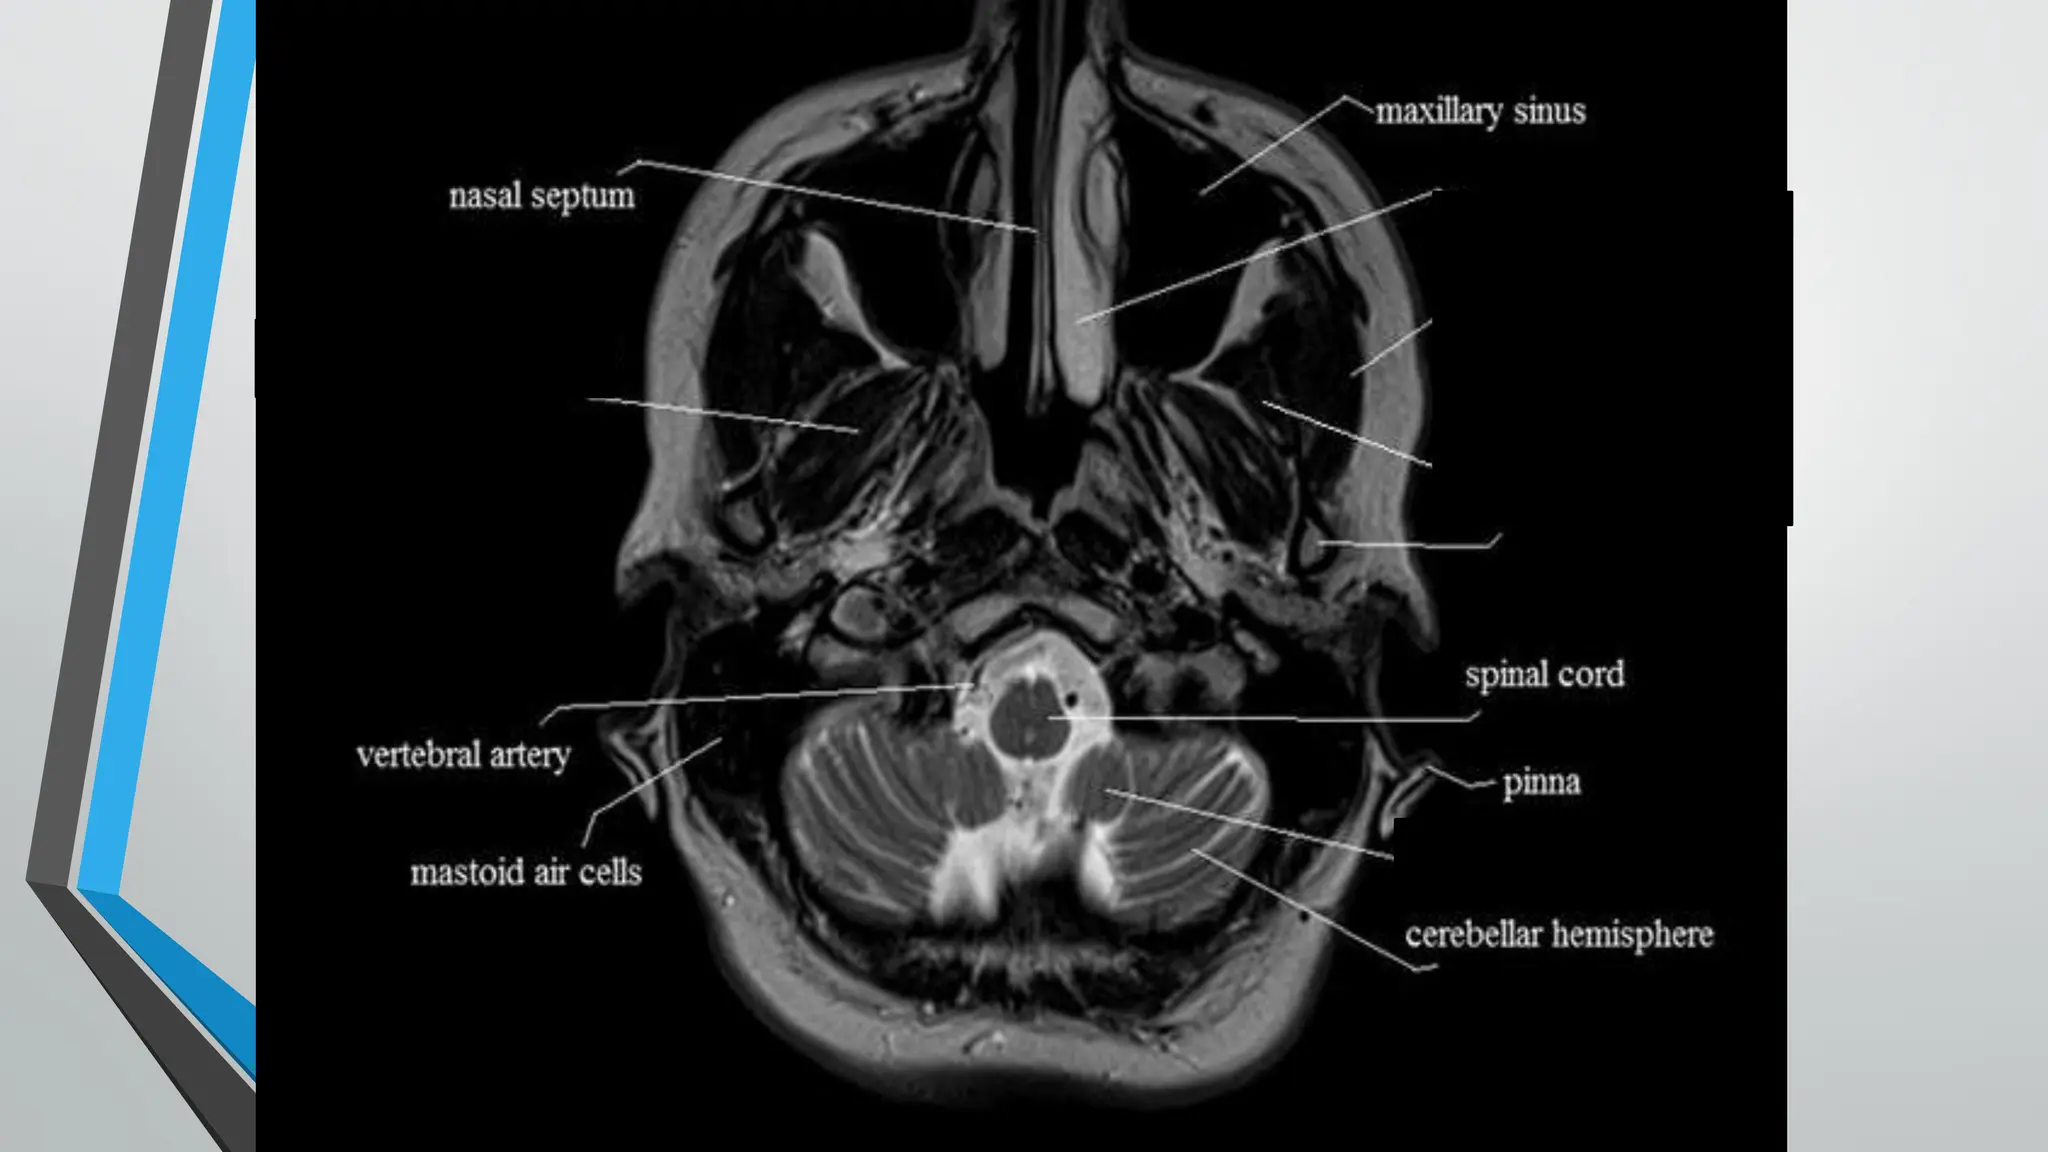

e-Anatomy is a high-quality anatomy and imaging content atlas.It is the most complete reference of human anatomy available on the Web, iPad, iPhone and Android devices. Explore detailed anatomical views and multiple modalities (over 8,900 anatomic structures and more than 870,000 translated medical labels) with images in CT, MRI, radiographs, anatomical diagrams and nuclear images. Visible Human Male. The Visible Human Male data set consists of MRI, CT, and anatomical images. Axial MRI images of the head and neck, and longitudinal sections of the rest of the body were obtained at 4mm intervals. The MRI images are 256 by 256 pixel resolution with each pixel made up of 12 bits of gray tone.